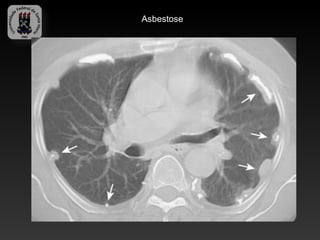

-ASBESTOSE

-Inalação de fibras de asbestos

-TC:

-   Placas e calcificações pleurais

-   Espessamento septal interlobular e intralobular,

-   Opacidades em vidro fosco

-   Bandas parenquimatosas

-   Faveolamento

Asbestose